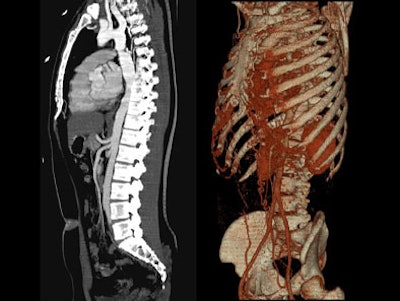

- On sagittal MIP images, the morphology of coarctation along with a captured left subclavian artery was demonstrated. Volume-rendered images showed hypertrophied internal mammary arteries and epigastric arteries. [Figures 3, 4, 5] [Movie 1]

| Figure 3. |